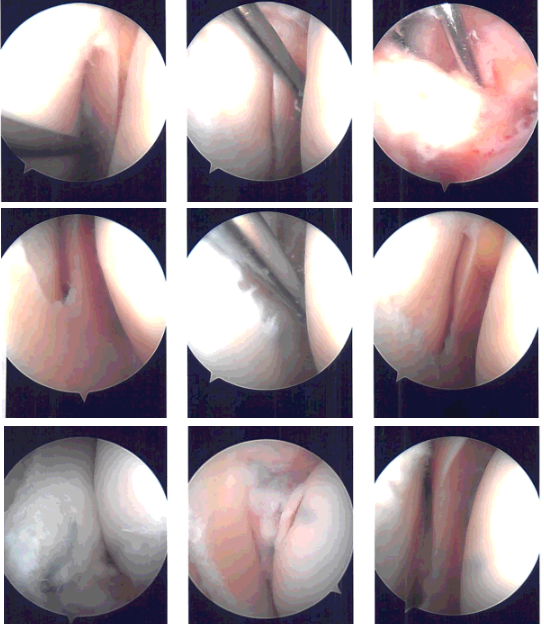

Lateral entry portal was made. Arthroscope was introduced. There were grade 2 to grade 3 osteoarthritic changes on the posterior surface of the patella on the lateral facet. There were loose cartilage fragments in the medial gutter. Examination of the medial compartment showed medial meniscus tear.

The medical entry portal was made using a spinal needle. A shaver was used to clear the joint as well as the meniscus. Biters were used sequentially to do the medial meniscectomy in the mid portion of the body.

The posterior root of the meniscus was found to be loose and on further examination, it was found that it was torn from the whole knee attachment. A decision was done to do a repair of the meniscal root. Examination of the Intercondylar notch showed the ACL was intact.

Examination of the lateral tibiofemoral compartment showed fraying and tearing of the medial edge of the lateral meniscus, which was cleaned using the biter as well as the shaver. Examination of the patellofemoral compartment showed grade 3 to grade 4 osteoarthritic changes of the lateral trochlea as well as the lateral facet of the patella.

Chondroplasty was performed. The scope was entered from the medical portal to re-confirm the findings. Again, the scope was entered from the lateral portal and repair for the medial meniscus root was planned.

The Arthrex jig was used to make an entry portal from the medial tibial condyle into the posterior plateau. The FlipCutter was used to make a depression for the root to insert and abrade the bone intraarticularly. Knee Scorpion was used to pass two FiberLinks.

The FiberLinks were sutured through the canal using suture lasso. The sutures were put in tension and fixed to the tibia using SwiveLock #4.75. Final pictures were again taken and saved.

The knee was thoroughly irrigated. Microfracture of intertrochlear notch was done using the chondral pick set. Fat pad could be seen coming out of the microfracture. The knee was irrigated and drained. The knee was closed using # 4-0 nylon. A 30 cc of Naropin was injected into the knee.

Intraoperative Arthroscopy Images